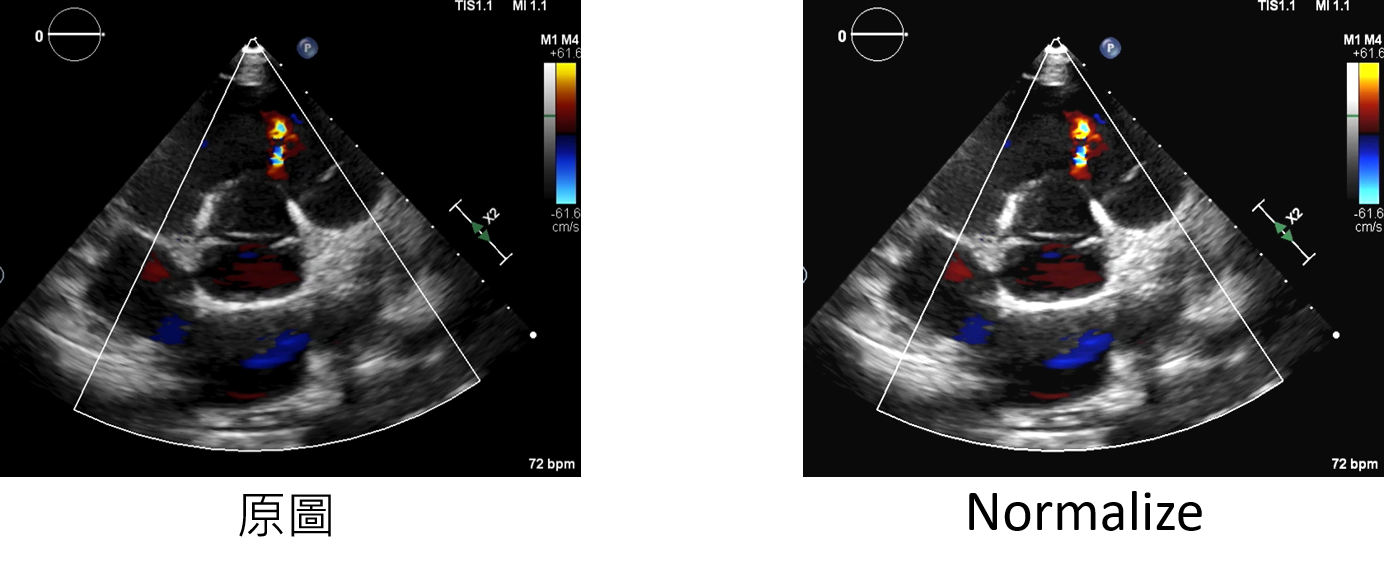

normalize:增強方法

輸入範例:

datagen=CustomDataGenerator(fun="normalize",dtype=int)